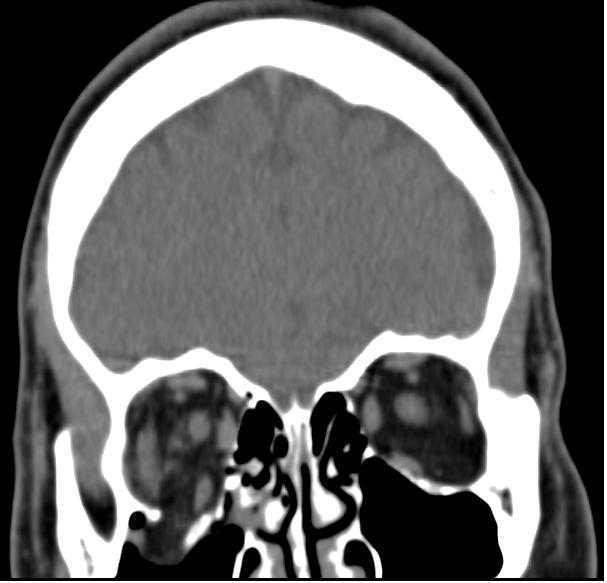

Laughlin Dawes, Radiopaedia.org. From the case rID: 35968

Sans incarcération musculaire :

- Demander un scanner avec des coupes coronales et consultation différée dans la semaine.

Avec trouble de l’élévation du regard (incarcération musculaire) :

- Demander un scanner avec des coupes coronales et appel urgent du CMF pour prise en charge dans les 6H.